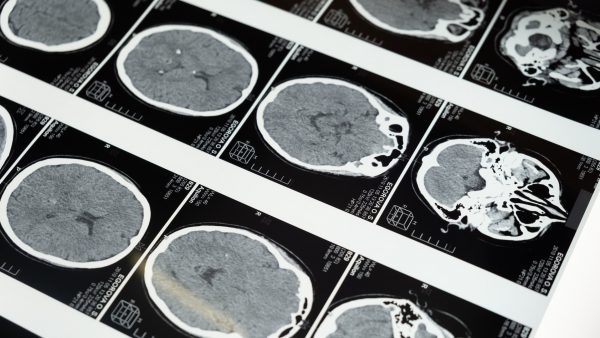

Diepe hersenstimulatie (Deep Brain Stimulation; DBS) is een behandeling die de motorische klachten (zoals het trillen van ledematen) bij de gevorderde fase van de ziekte van Parkinson kan verlichten bij sommige patiënten. Bij een operatie worden twee piepkleine elektroden in bepaalde delen van de hersenen geplaatst. Deze delen hebben een belangrijke functie bij het coördineren van bewegingen, emoties en of cognitieve functies. Die elektroden geven met behulp van een batterij stroomstootjes af. De signalen die problemen veroorzaken worden zo als het ware tegengehouden.

Bij een Deep Brain Stimulation operatie worden, via twee gaten in de schedel, twee elektroden diep in de hersenen geplaatst. De elektroden worden met onderhuidse kabeltjes verbonden met een neurostimulator, een klein apparaat. Deze neurostimulator komt onder het sleutelbeen of onderhuids in de buikstreek en geeft (een paar weken na de operatie) kleine stroomstoten af. De stroomstoten blokkeren signalen die bewegingsproblemen kunnen veroorzaken, zoals stijfheid en overbewegen.

Meestal komt een DBS in beeld als medicijnen of leefstijladviezen niet meer afdoende zijn. Om te bepalen of je in aanmerking komt voor de operatie, worden verschillende onderzoeken gedaan. Denk bijvoorbeeld aan een MRI-scan, lichamelijk, bloed- en neuropsychologisch onderzoek.